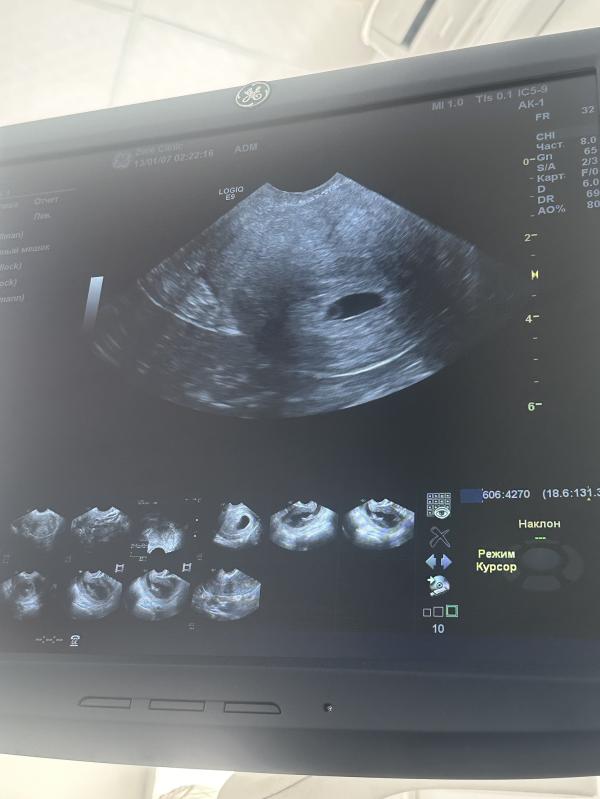

Сегодня ощущение хорошее, настроение хорошее, огромное чувство благодарности 🙏Не сказать, что аппетит сильный. Понимаю, что надо есть, и от этого ем. Сильного прям аппетита так такого нет. Сегодня сходила на УЗИ ради спокойствия себя понять появится второй эмбрион или уже нет , чтобы настроится правильно , и вот на сегодняшний день на УЗИ показало, что плодное яйцо размером 13,5 мм, желточный мешок 2,5 мм и КТР 2,4 мм. Сердцебиение пока не визуализируется. В матке только один эмбрион. Все хорошо, никаких гематом, все хорошо.